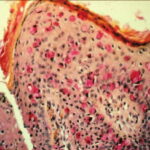

PATHOLOGY The intraepidermal adenocarcinoma of EMPD and MPD has a similar histologic appearance. There are groups, clusters, or single cells within the epidermis that show nuclear enlargement with atypia, prominent nucleoli, and well-defined ample cytoplasms . Intercellular bridges are absent. The cells can be within all levels of the epidermis and can compress but preserve the basal layer without junctional nest formation. The cells can extend into the contiguous epithelium of hair follicles and sweat gland ducts. Acanthosis, hyperkeratosis, and parakeratosis are often present. These cells have a “pagetoid” appearance and simulate other intraepidermal malignancies, including melanoma, pagetoid squamous cell carcinoma in situ, mycosis fungoides, cutaneous adnexal carcinomas (sebaceous carcinoma, porocarcinoma, and others), Merkel cell carcinoma, Langerhans cell histiocytosis, and other epidermotropic cutaneous metastases. The cells of MPD and EMPD can be pigmented, which should not necessarily indicate they are melanocytic. Paget's cells have intracellular mucopolysaccharides, with EMPD having a greater amount of mucin as compared